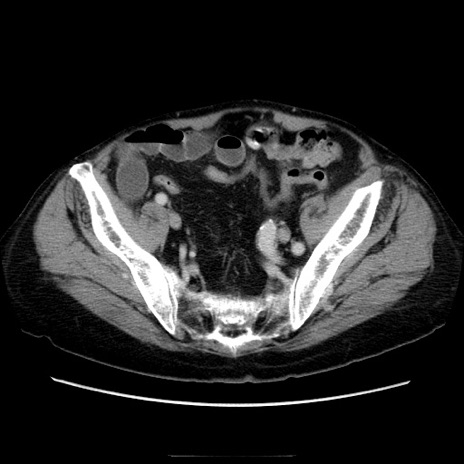

症例21(横断像)

【症例】70歳代男性

【主訴】腹痛

【現病歴】肝硬変・肝細胞癌にてかかりつけの方。約9時間前に食後より腹痛出現。症状が徐々に増悪し、嘔吐出現したため来院。

【既往歴】肝硬変、肝細胞癌(RFA、TACE後)

【身体所見】意識清明、表情苦悶様、BT 36℃、BP 129/78mmHg、P 88bpm、SpO2 97%(RA)、右上腹部から心窩部にかけて圧痛あり、反跳痛なし、筋性防御あり。

【データ】WBC 5800、CRP 0.16